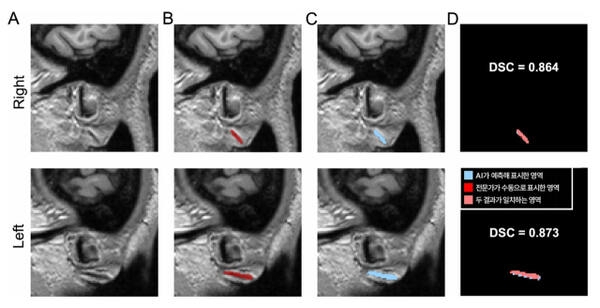

3차원 원본 이미지(A)를 토대로 전문가가 수동으로 직접 표시한 주름(B)과 AI가 예측해 자동으로 표시한 영역(C). DSC 값은 두 영역의 겹침 정도를 수치화한 것으로, AI가 전문가와 거의 일치하게(약 87%) 주름을 찾아냈다는 의미를 가진다. 분당서울대병원 제공

그 결과 전문가가 수동으로 표시한 영역과 AI가 자동으로 분할한 영역의 일치 정도를 측정하는 DSC(Dice 유사도 계수, 1에 가까울수록 유사) 값이 두 차례의 검증에서 0.734, 0.714로 나타났다. 이는 AI가 찾아낸 영역이 전문가의 판단과 70% 이상 부합한다는 뜻으로, 의료영상 분야에서 높은 수준으로 인정받는다.